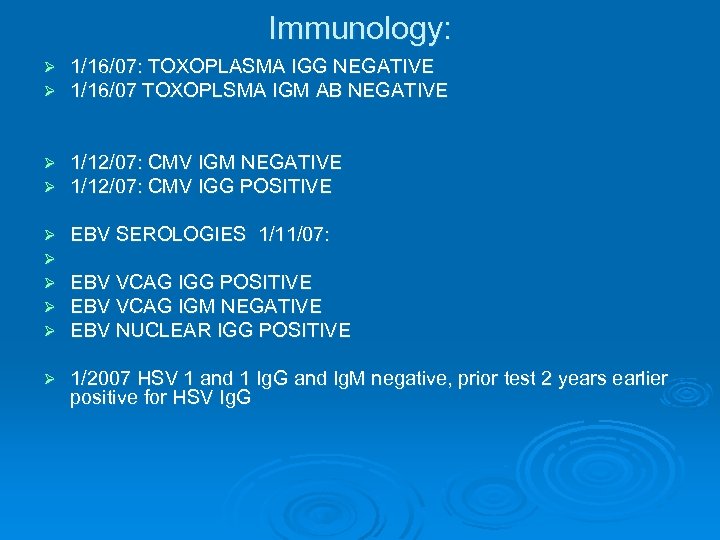

Immunology: Ø Ø 1/16/07: TOXOPLASMA IGG NEGATIVE 1/16/07 TOXOPLSMA IGM AB NEGATIVE Ø Ø 1/12/07: CMV IGM NEGATIVE 1/12/07: CMV IGG POSITIVE Ø Ø Ø EBV SEROLOGIES 1/11/07: Ø 1/2007 HSV 1 and 1 Ig. G and Ig. M negative, prior test 2 years earlier positive for HSV Ig. G EBV VCAG IGG POSITIVE EBV VCAG IGM NEGATIVE EBV NUCLEAR IGG POSITIVE